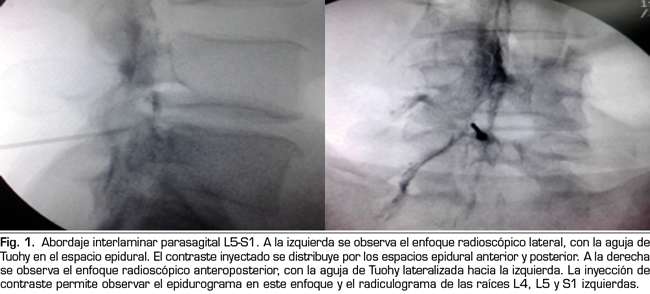

Figura 1